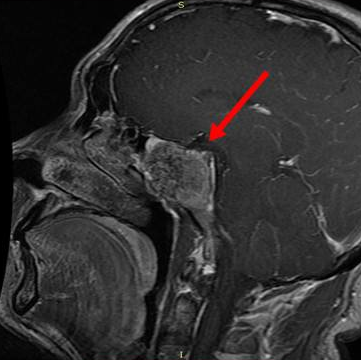

• 77岁斜坡脊索瘤头痛、复视,全切术后1年肿瘤没有复发

77岁斜坡脊索瘤头痛、复视,全切术后1年肿瘤没有复发

2022-07-07 15:00:08

77岁斜坡脊索瘤头痛、复视,全切术后1年肿瘤没有复发 脊索瘤是脊索的残余,起源于骨骼,可以发生在沿颅脊轴的任何地方。脊索瘤的发病率为十万分之...